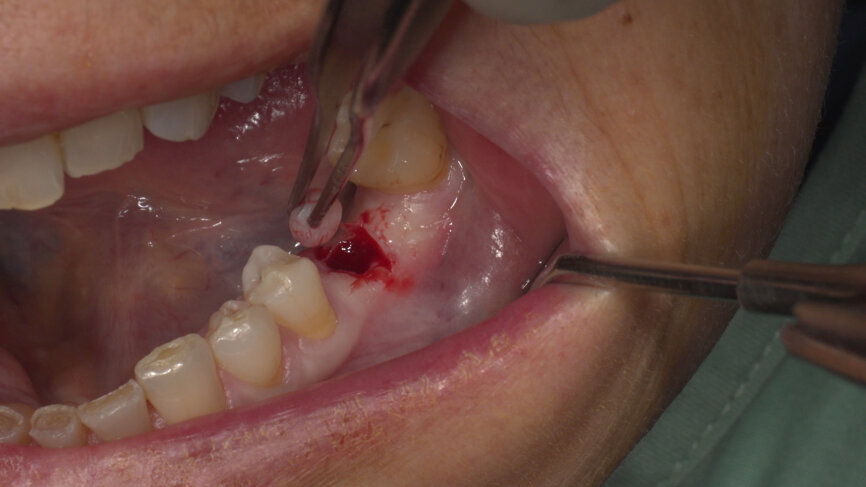

Under local anaesthesia, a flapless implant surgery technique was performed in position #36. Owing to the quality of the bone, staged drilling with continuous saline irrigation was performed in order to obtain a proper, safe insertion torque (Figs. 2–7). One implant (BLT, Regular Neck, Roxolid, ⌀ 4.8 × 10.0 mm) was placed, and a torque of 42 N cm was applied (Figs. 8–11).